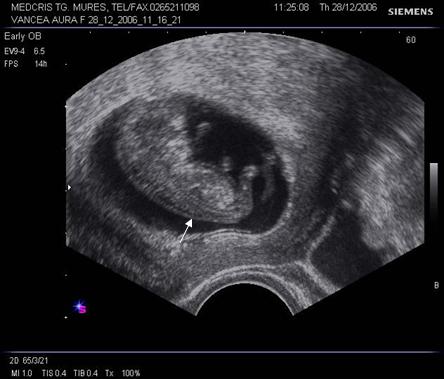

Fig. Nr.7. Sac gestational intrauterin ( cu sageata ) la ecografia transvaginala, coroana trofoblastica